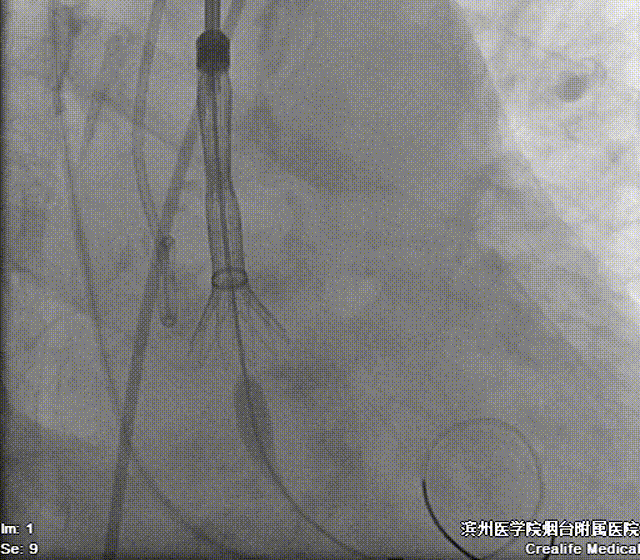

22mm球囊预扩影像示双侧冠脉灌注良好,无明显腰征,决定植入AV26号瓣膜。

造影辅助下精准释放

左侧腋动脉入路建立后,团队密切配合,高效完成了跨瓣、球囊预扩操作。22mm球扩影像示双侧冠脉灌注良好,无明显腰征,决定植入AV26号瓣膜。输送器过弓顺利。在瓣膜定位过程中,通过善用造影辅助,我们成功将瓣膜定植于预定释放位(瓣环下约3mm处)。瓣膜释放后形态规整,工作状态良好,未发生明显位移。